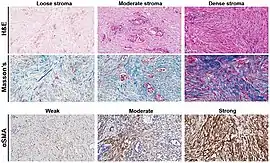

Characteristics of desmoplastic stromal response

A desmoplastic response is characterized by larger stromal cells with increased extracellular fibers and immunohistochemically by transformation of fibroblastic-type cells to a myofibroblastic phenotype.[2] Myofibroblastic cells in tumors are differentiated from fibroblasts for their positive staining of smooth-muscle actin (SMA).[2] Furthermore, an increase in total fibrillar collagens, fibronectins, proteoglycans, and tenascin C are distinctive of the desmoplastic stromal response in several forms of cancer.[14] Expression of tenascin C by breast cancer cells has been demonstrated to allow for metastasis to the lungs and cause the expression of tenascin C by the surrounding tumor stromal cells.[15] In addition, tenascin C is found extensively in pancreatic tumor desmoplasia as well.[16]

Differentiation of scars

The stroma of the prostate is characteristically muscular.[2] Due to this muscularity, detecting the myofibroblastic phenotypic change indicative of reactive stroma is difficult in an examination of patient pathologic slides.[2] A diagnosis of reactive stroma associated with prostate cancer is one of poor prognosis.[2]